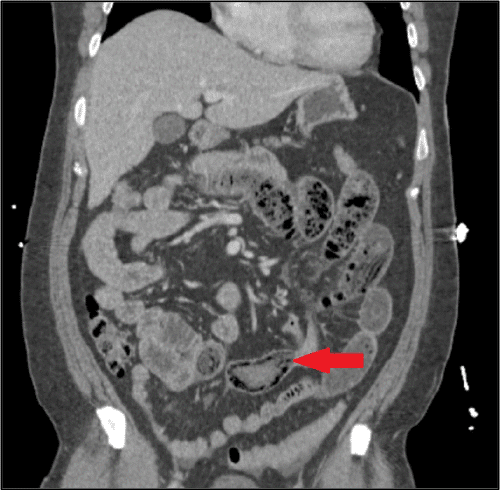

A partially edentulous and otherwise healthy 46-year-old man presented to the hospital with severe waxing-and-waning abdominal pain, nausea, and vomiting for the past two days. The pain was localized in the epigastrium and was unrelieved by sitting or standing. He was afebrile on arrival, and his vital signs were within normal limits. Physical examination showed a soft, rotund abdomen with tenderness in the epigastrium upon palpation. Laboratory studies were notable for a white blood cell count of 18.4 × 103 cells/μL (normal range: 4.5-11.0) and a venous lactate of 3.81 mmol/L (normal range: 0.40-1.30). Subsequent CT scan demonstrated an obstructing intraluminal mass in the left lower quadrant, with dilated loops of bowel proximal to the transition point and and signs suggestive of possible bowel ischemia, including pneumatosis and mesenteric edema.

Figure 1. Abdominopelvic CT with Contrast (coronal view). Published with Permission

Red arrow points to an obstructing intraluminal mass in the distal small bowel